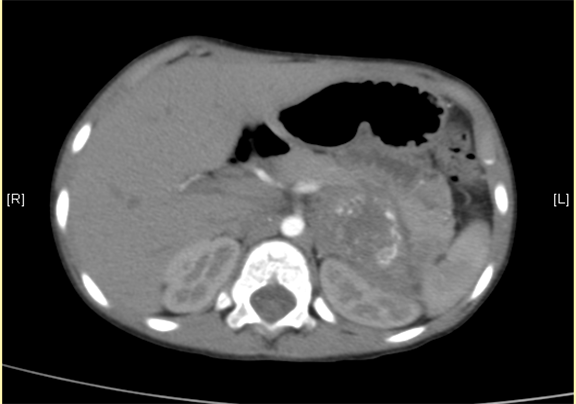

下腹部增强CT示:神经母细胞瘤。

将0.625mm双源薄层CT资料的静脉期和动脉期Dicom格式文件导入海信CAS系统。

通过调节窗宽窗位调整CT序号,对肿瘤,肝实质,胆囊,下腔静脉,肿瘤,肝动脉、门静脉及肝静脉等进行三维重建;系统自动计算肿瘤体积和肝脏体积。

术前CT检查:

平衡期